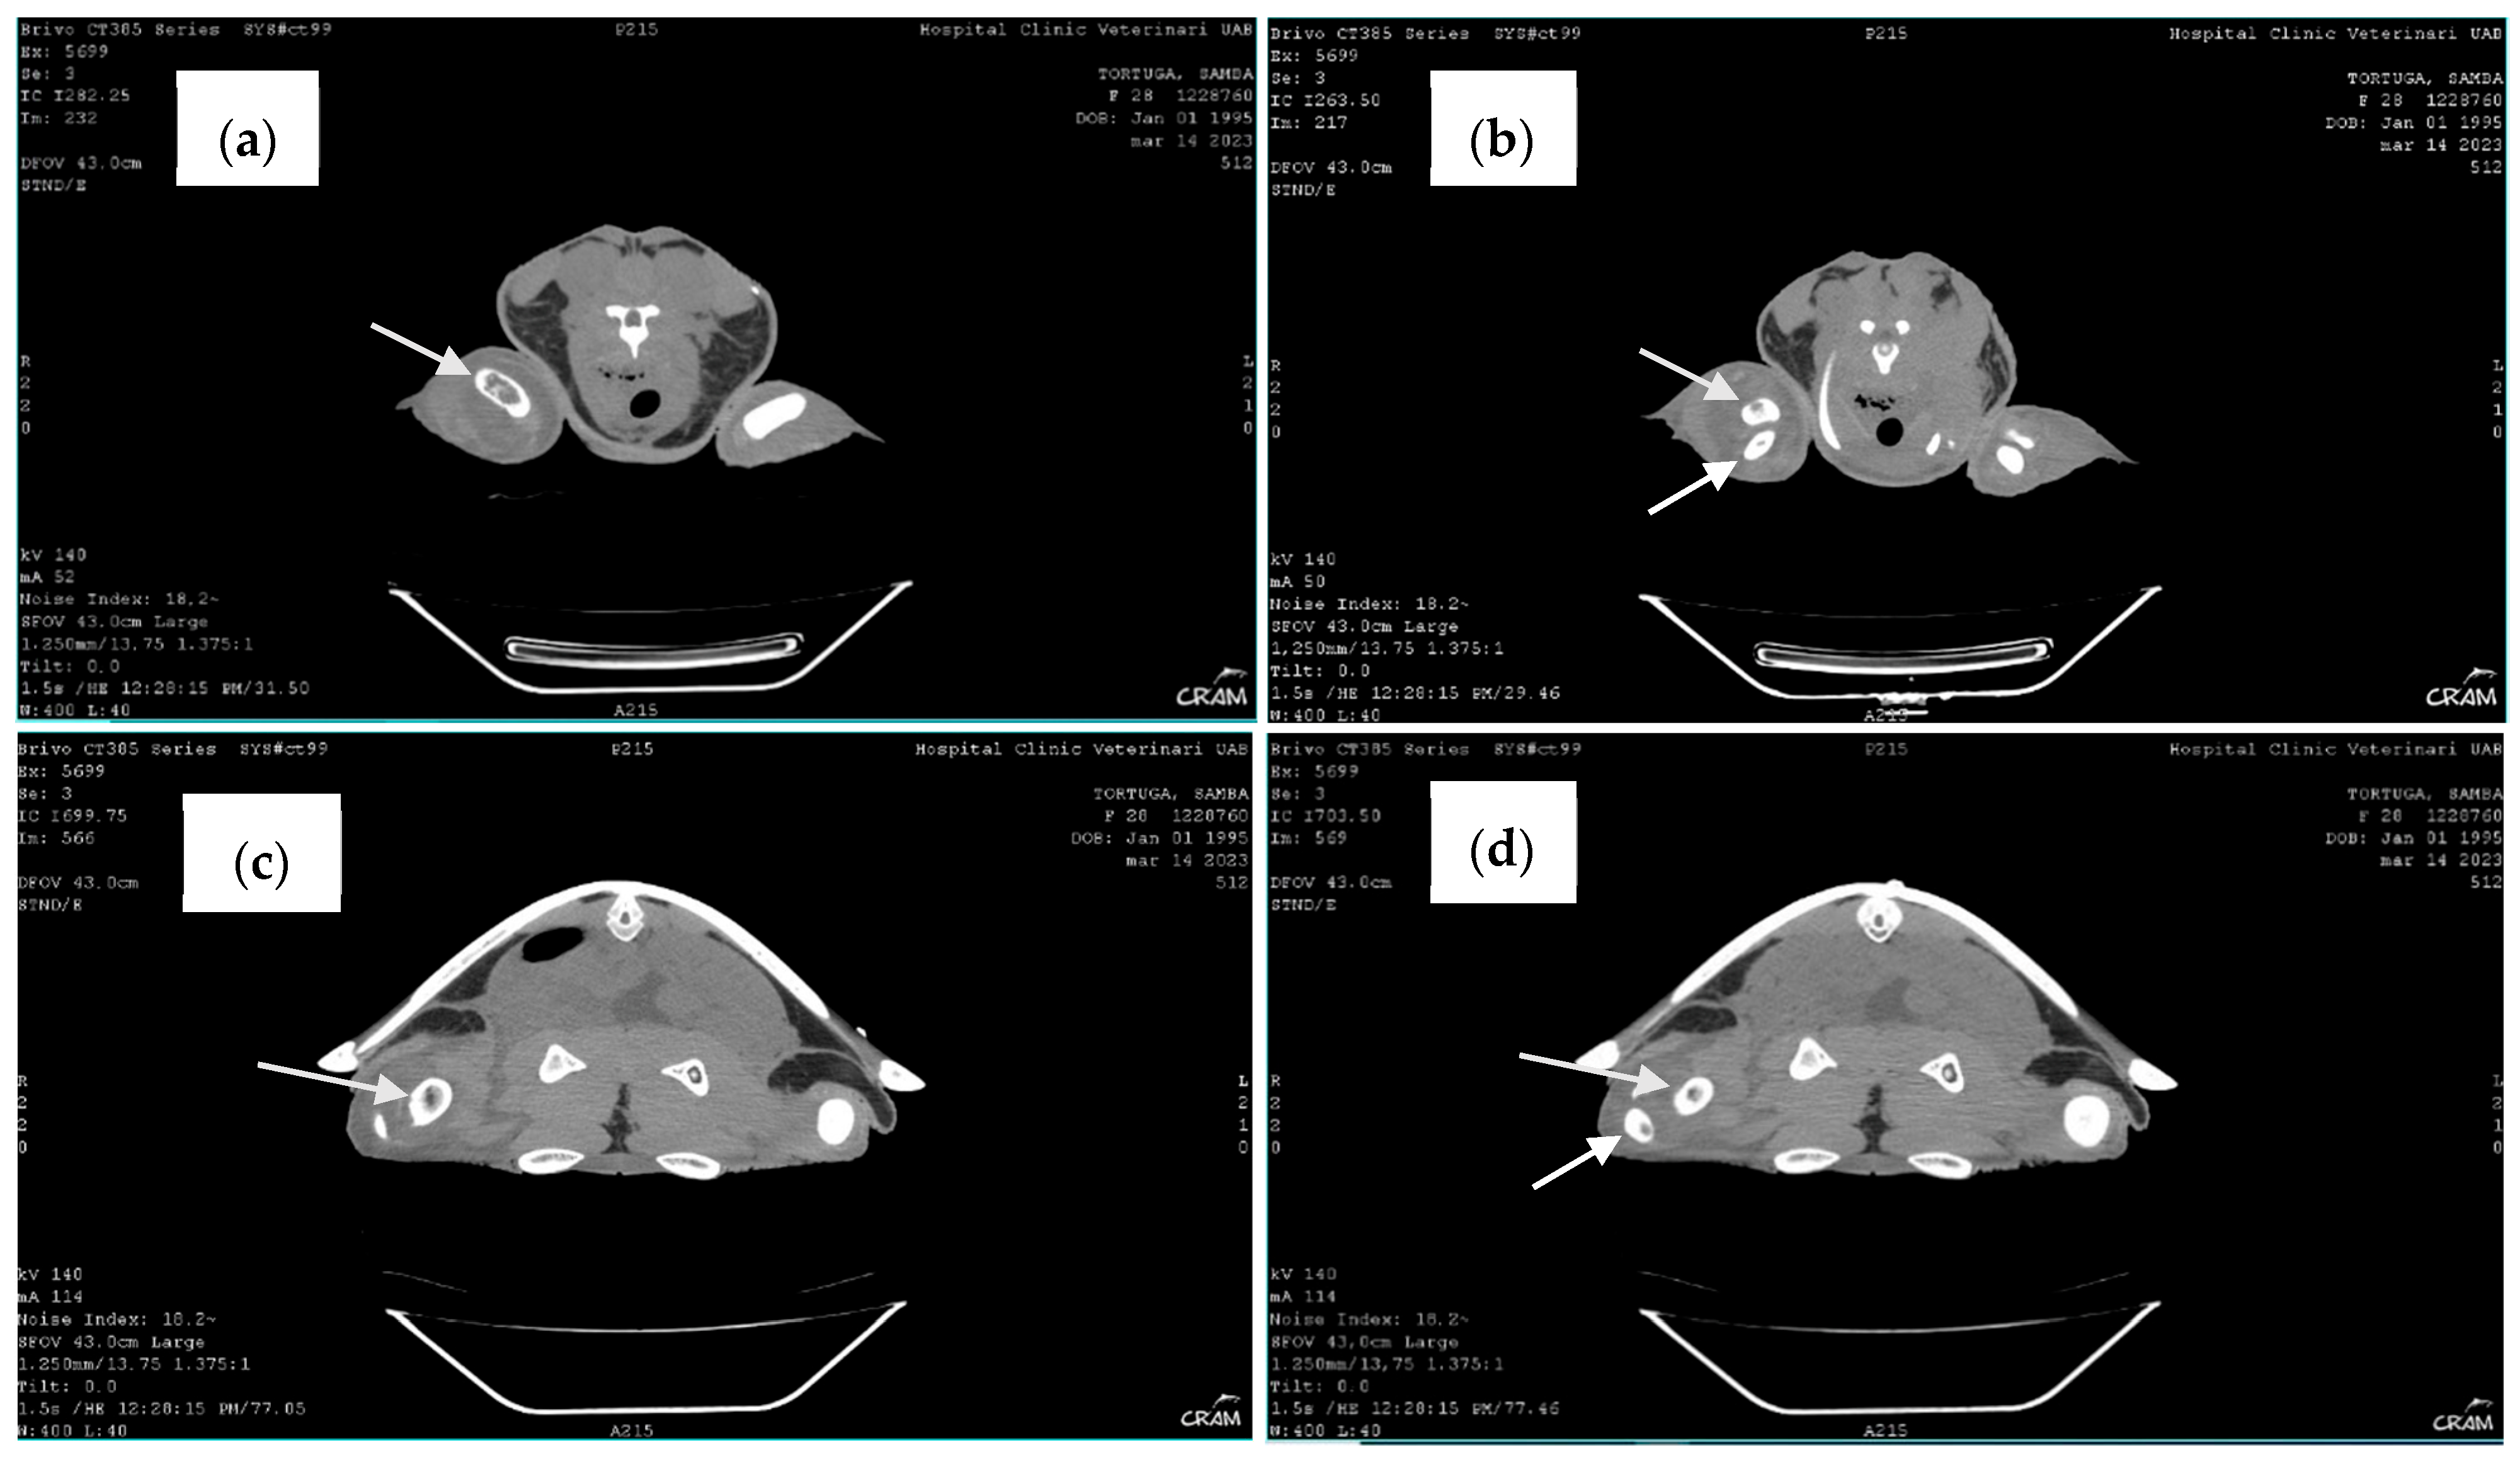

Therefore, to better visualize the lesions, computed tomography (CT) of the whole body, in soft tissue and bone algorithm, with 1.25 mm thick sections, without administration of intravenous iodinated contrast, was performed. CT confirmed the lytic lesions observed in radiography on the distal right humerus, proximal right radius and ulna, distal right femur, and proximal right tibia and fibula. When clinical signs appeared, blood culture at 24–26 °C with antibiogram was performed, revealing a positive result.

Late-stage lesions after five months of rehabilitation were characterized by sclerosis and remodeling of the lesion borders (Figure 7). Lesions occurring within the bone shaft typically remain asymptomatic. However, those adjacent to the joint surface, known as juxta-articular lesions, may advance to structural deterioration of the joint surface, leading to symptoms such as pain and restricted movement. CT revealed additional lytic bone lesions of the left ischium, ileum, and pubis; right ischium; left humerus head; and confirmed the lytic lesions observed via radiography (Figure 8). Throughout the treatment period, the animal continued to have a healthy appetite and was bright and alert according to Manire et al. 2017, Sea Turtle Health & Rehabilitation [22]. Blood samples were taken once a month to evaluate hematological and biochemical values, and all the parameters were in range according to plasma biochemical and hematological baseline values in loggerhead sea turtles from the Mediterranean Sea proposed by Basile et al. (2011) [19].

Figure 8. Computed tomography. Note bone lysis on the distal end of the right humerus (arrow) (a), the proximal end of the right radius and ulna (arrows) (b), and the proximal end of the right tibia and fibula (arrows) (c,d).